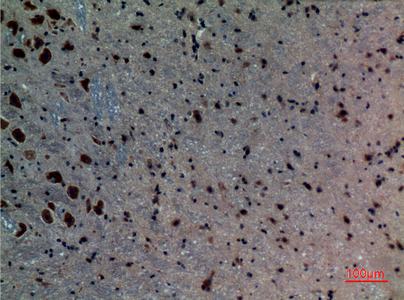

Total ALK-1 Cell-Based Colorimetric ELISA Kit

ELISA

Colorimetric

catalytic activity:ATP + [receptor-protein] = ADP + [receptor-protein] phosphate.,cofactor:Magnesium or manganese.,disease:Defects in ACVRL1 are the cause of hereditary hemorrhagic telangiectasia type 2 (HHT2) [MIM:600376]; also known as Osler-Rendu-Weber syndrome 2 (ORW2). HHT2 is an autosomal dominant multisystemic vascular dysplasia, characterized by recurrent epistaxis, muco-cutaneous telangiectases, gastro-intestinal hemorrhage, and pulmonary, cerebral and hepatic arteriovenous malformations; all secondary manifestations of the underlying vascular dysplasia.,function:On ligand binding, forms a receptor complex consisting of two type II and two type I transmembrane serine/threonine kinases. Type II receptors phosphorylate and activate type I receptors which autophosphorylate, then bind and activate SMAD transcriptional regulators. Receptor for TGF-beta. May bind activin as well.,similarity:Belongs to the protein kinase superfamily. TKL Ser/Thr protein kinase family. TGFB receptor subfamily.,similarity:Contains 1 GS domain.,similarity:Contains 1 protein kinase domain.,